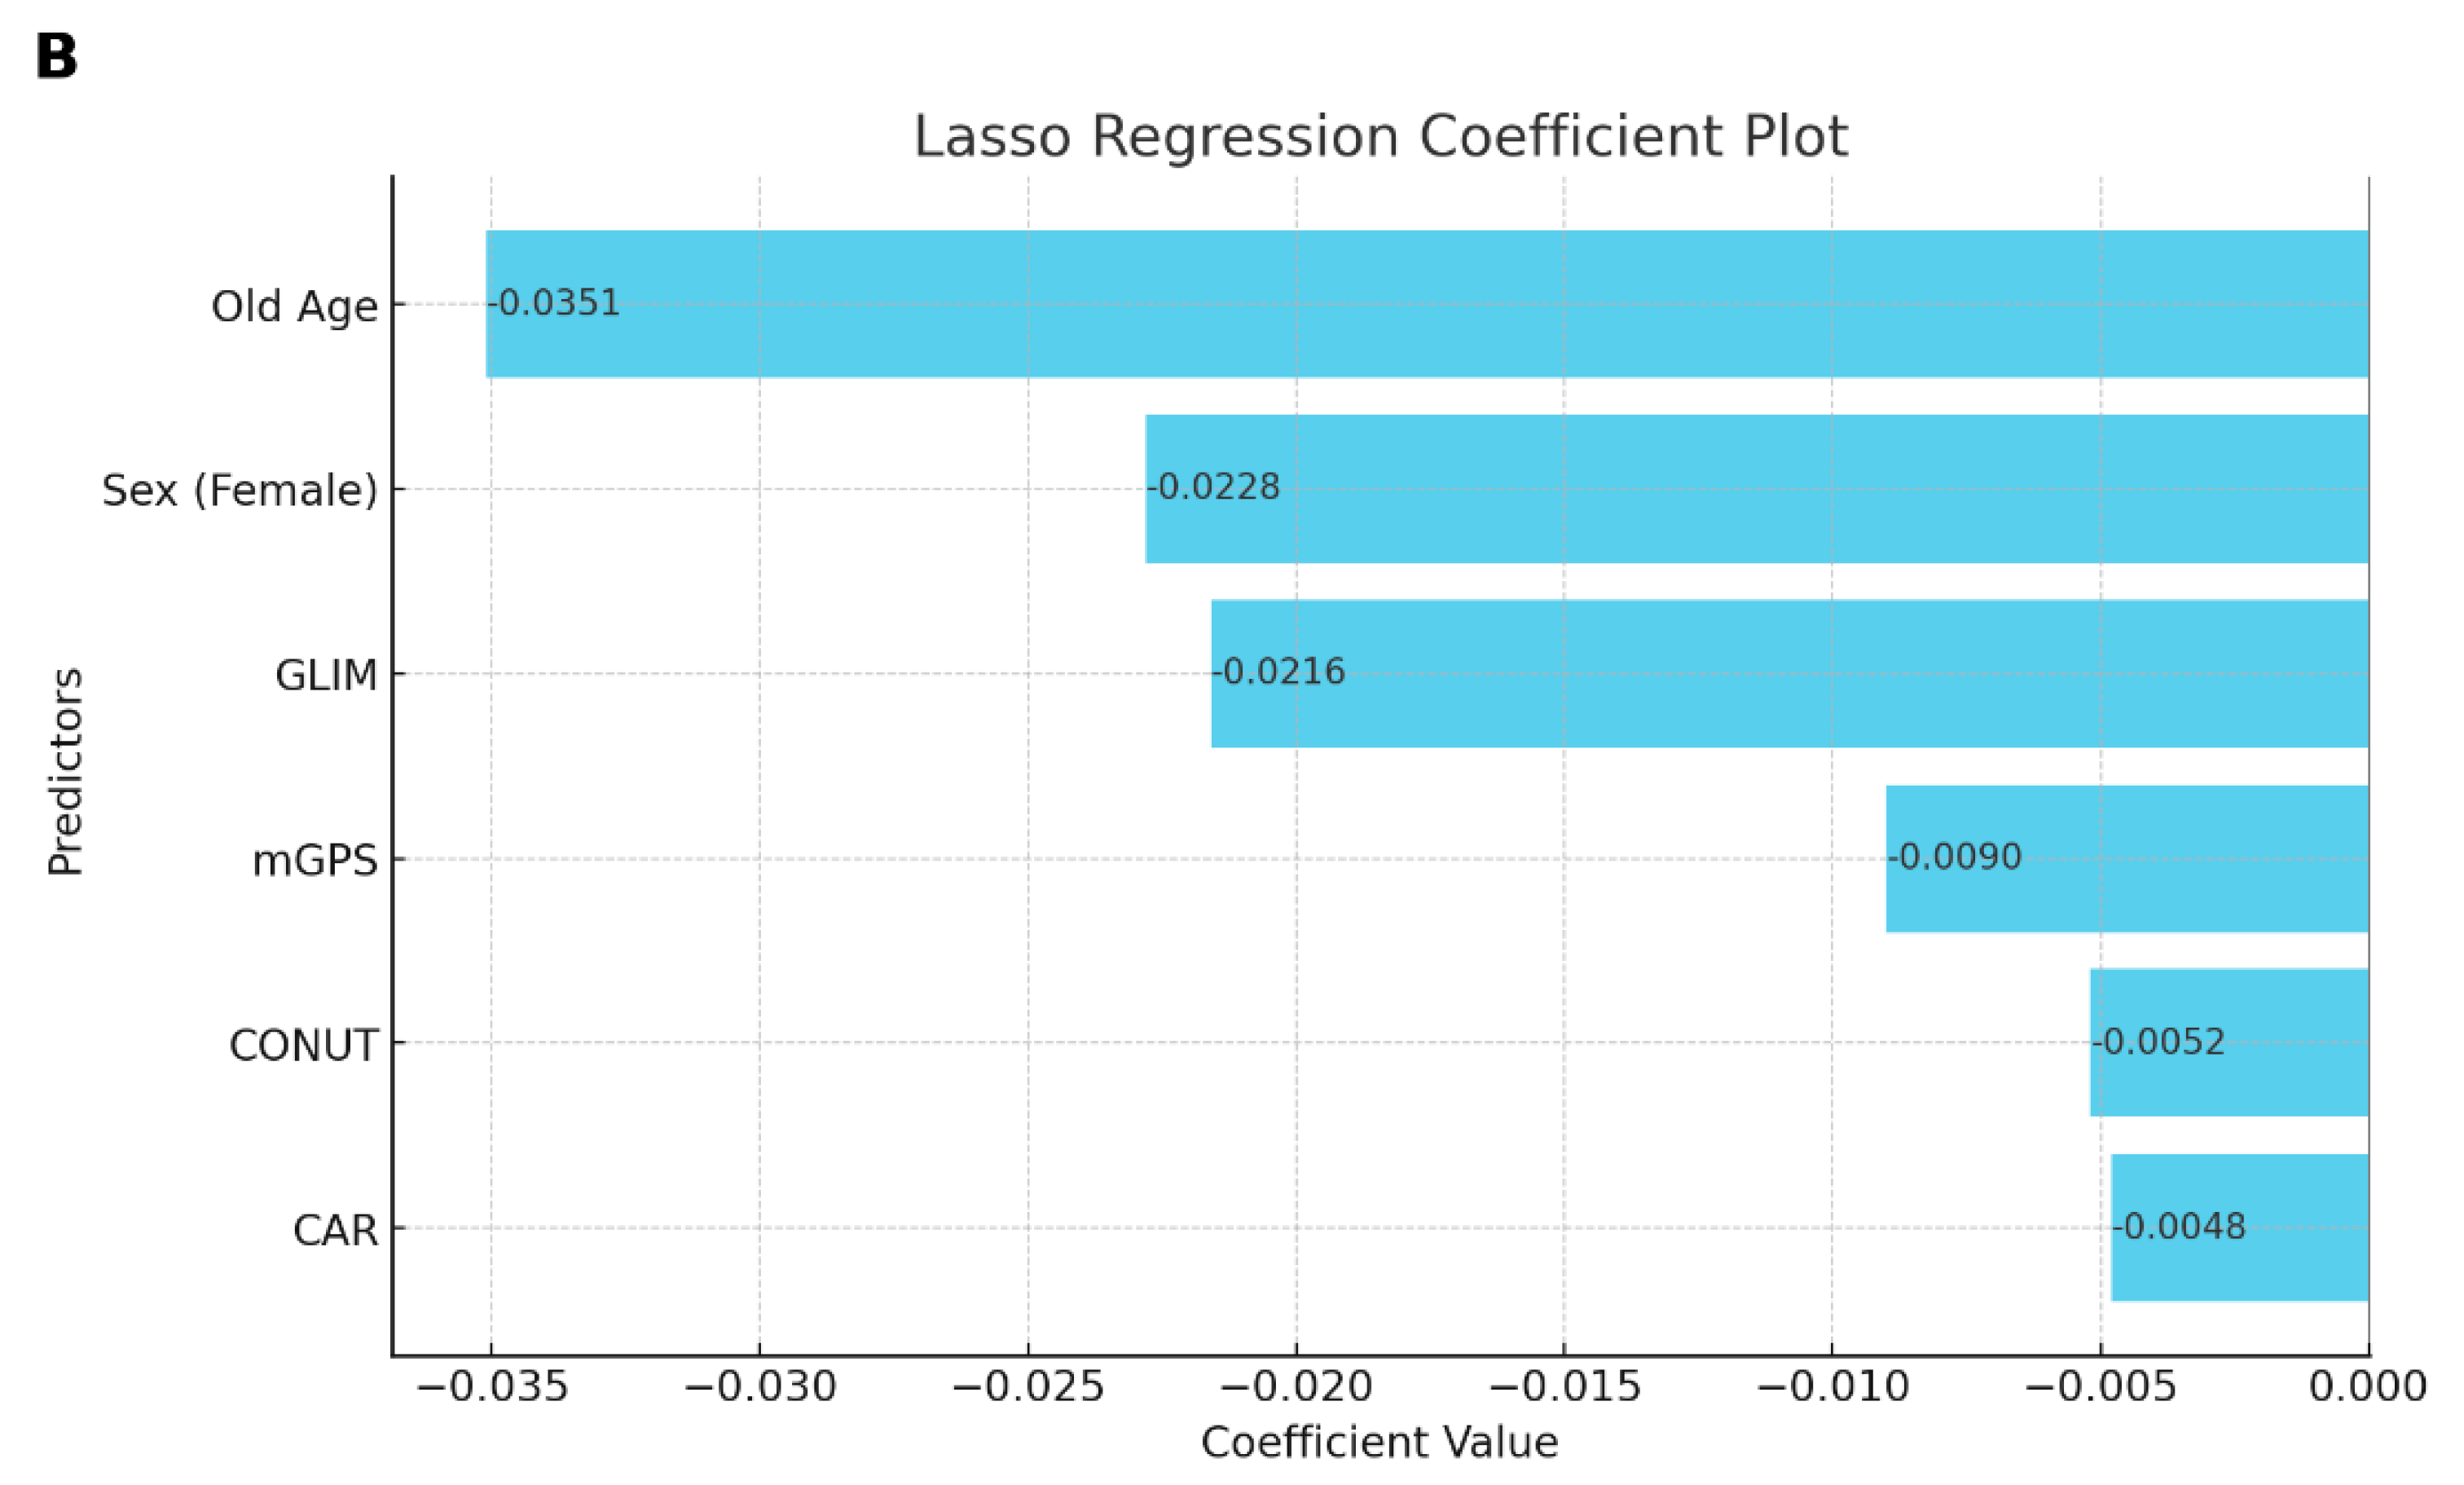

| CAR | 0.10 ± 0.06 | 0.19 ± 0.10 | 0.14 ± 0.09 | 0.14 ± 0.24 | |

| CONUT score | |||||

| Normal (0–1) | 29 (56.86%) | 25 (58.14%) | 9 (40.91%) | 63 (54.32%) | 0.806 ± 0.201 |

| High (≥2) | 22 (43.14%) | 18 (41.86%) | 13 (59.09%) | 53 (45.68%) | 0.778 ± 0.199 |

| mGPS | |||||

| Low risk | 46 (90.2%) | 33 (76.74%) | 16 (72.73%) | 95 (81.90%) | 0.814 ± 0.188 |

| Intermediate risk | 5 (9.8%) | 7 (16.28%) | 5 (22.73%) | 17 (14.66%) | 0.710 ± 0.218 |

| High risk | 3 (6.98%) | 1 (4.55%) | 4 (3.45%) | 0.555 ± 0.314 | |